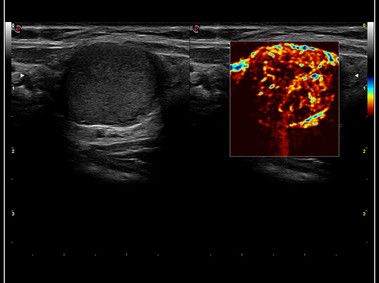

In ambito diagnostico si occupa di Ecografia, Eco-Color-Doppler, Radiologia e Neuroradiologia (TC ed RM).

- Ecografia dell'addome completo, Ecografia dell'addome superiore o inferiore, Ecografia ed Eco-Color-Doppler della tiroide, Ecografia dei linfonodi / delle stazioni linfonodali (collo, ascelle, inguine, altri distretti), Ecografia prostatica, Ecografia dei reni e surreni, Ecografia testicolare (varicocele), Ecografia dei tessuti molli (studio lesioni cutanee, cisti, etc..), Ecografia articolare, Ecografia muscolo-scheletrica.

- Eco-Color-Doppler (ECD) dei tronchi sovra-aortici (TSA), ECD dell'aorta addominale e dei vasi iliaci, ECD aorto-iliaco, ECD celiaco-mesenterico, ECD degli arti inferiori arterioso o venoso, ECD degli arti superiori arterioso o venoso, ECD testicolare, ECD delle arterie temporali, ECD trans-cranico senza mdc.